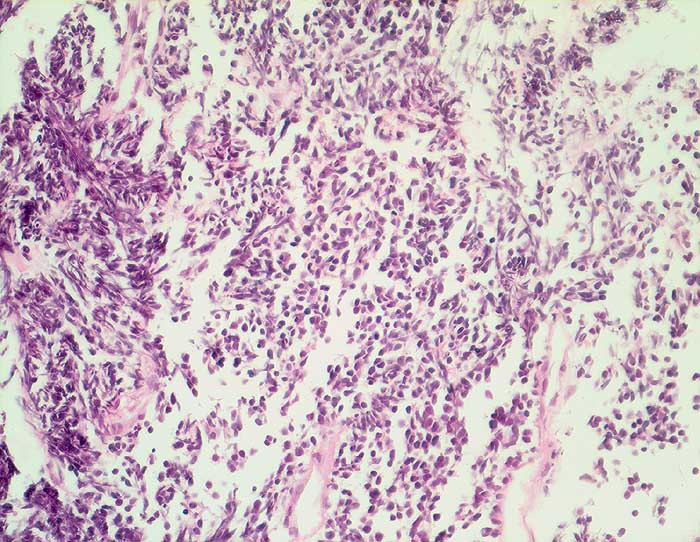

n/ Kleinzelliges Bronchuskarzinom

Kleinzelliges Bronchuskarzinom

Der Nachweis des kleinzelligen Karzinoms gelingt im Sputum meist leichter als im Bronchialsekret. Im Bronchialsekret sind die Tumorzellen oft zwischen Flimmerzellen und Entzündungszellen versteckt, während die stark hyperchromatischen Kerne im Sputum schon bei schwacher Vergrösserung ins Auge fallen. Die fast nacktkernigen Zellen liegen einzeln oder bilden schmale zeilenförmige Verbände und Haufen. Innerhalb der Verbände schmiegen sich die Kerne eng aneinander (=molding). Die Kerne sind zwei- bis dreimal so gross wie Lymphozyten. Im Sputum erscheinen die Karzinomzellen kleiner als im Feinnadelpunktat, Bürstenabstrich oder Bronchialsekret.

Basalzellen sind monomorpher und bilden kleine, regelmässige kompakte Verbände. Lymphomzellen liegen stets einzeln. Feindisperse Chromatinverteilung und zeilenförmige Verbände sprechen gegen ein Lymphom. In Zweifelsfällen erfolgt die Unterscheidung immunzytochemisch (Panzytokeratin und CD45).

Das ersten Beispiel zeigt ein Bronchialsekret, das zweite eine Bronchialbürstenzytologie.